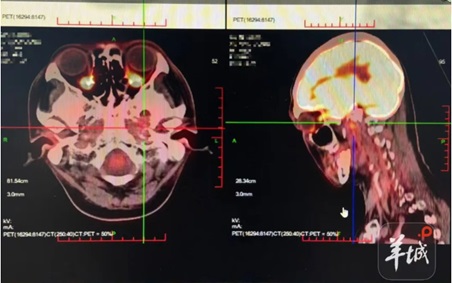

国产BNCT设备精准抗癌,首例患者肿瘤影像学复查已完全消失|一线探“新”

硼中子俘获治疗技术

近年来肿瘤治疗领域最新的精准治疗技术,被医学界称为肿瘤治疗领域继手术、传统放疗、抗癌药物、免疫治疗之后的“第五疗法”。临床中对于复发性、浸润性、局部转移肿瘤等具有突出的优势;目前已有数千例临床案例,证明在头颈癌、恶性脑瘤、黑色素瘤等多种实体肿瘤上展现出优异的疗效。 普利制药与中科高能所合作,开发的多种使用硼中子俘获疗法,用于脑胶质瘤、肾癌、宫颈癌治疗的新型硼药项目,目前处于优化阶段,进展顺利。